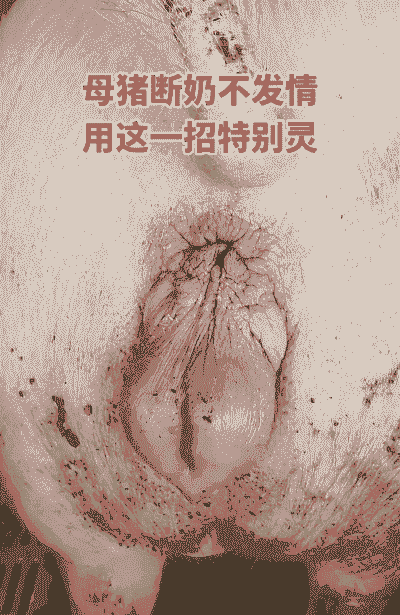

母猪产后恶露的颜色变化是判断其健康状况的重要指标之一。正常情况下,母猪产后恶露的颜色会经历以下几个阶段:

产后第1天 :恶露通常为大量稀薄的液体。

产后3天左右:

恶露颜色逐渐变为少量白色牛奶样。

产后3天后:

恶露量减少,颜色可能变为白色或透明清亮。

除了颜色变化,恶露的浓稠度和臀部结痂情况也需要关注。产后3天内流出的脓汁越浓,臀部结痂多,可能意味着子宫内膜炎的概率越大,病情也越严重。